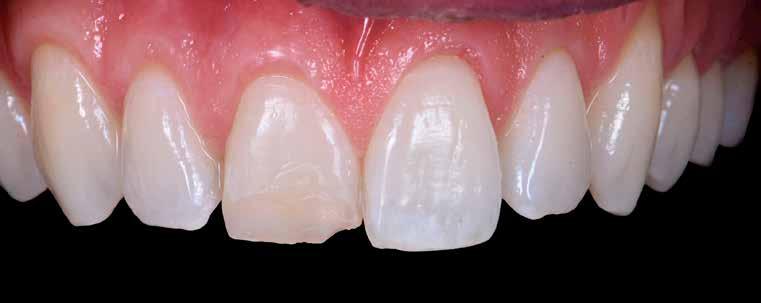

Az UR1 elszíneződött, és palatálisabb helyzetben van, mint az ellenoldali központi UL1 (2. ábra)

3. ábra: Az esztétikai elemzés a gingivális zenit aszimmetriáját mutatja. – 4. ábra: Az UR1 izolálása kofferdámmal.

5. ábra: Törött kompozit-helyreállítás eltávolítása. – 6. ábra: Matrica és adhézió használata 3 lépéses etch&rinse rendszerrel.

7. ábra: A vesztibuláris kiemelkedési profil helyreállítása zománcszínű kompozittal. – 8. ábra: A palatinális fal helyreállítása zománcszínű kompozittal.

9. ábra: A dentin anatómiájának helyreállítása átlátszatlan dentinszínű kompozittal. – 10. ábra: Világoskék és fehér effektszínek használata.

11. ábra: A rétegezés véglegesítése zománcszínnel. – 12. ábra: Az UL1 átmenő vonalainak emulálása finírozás közben.

A kezelés napján, helyi plexusérzéstelenítést követően, az UR1-et kofferdámmal izoláljuk, kiterjesztve az izolációt az első premolárisokra (4. ábra)

Ezt követően eltávolítjuk a törött kompozt-helyreállítást, és az előkészített fogon rövid ferdére preparálást készítünk, majd az UR1 teljes felületén homokfúvást végzünk 27 μm-es alumínium-oxid porral (5. ábra)

A megváltozott passzív erupció korrigálása érdekében úgy döntöttünk, hogy a fog kiemelkedési profilját a vesztibuláris kidomborodás hangsúlyozásával és az ellenoldali elemmel való szimmetriára törekvéssel újra létrehozzuk. Erre a célra

egy előre megformázott fémmatricát használunk, amelyet két ékkel blokkolunk.

A matrica adaptálása után az adhéziós eljárásokat egy 3 lépéses etch&rinse rendszerrel végezzük. Minden egyes lépést 40 másodperces, UV-fénnyel történő polimerizálás követ (6. ábra)

A vesztibuláris kiemelkedési profilt zománcszínű kompozittal (a TOKUYAMA DENTAL ESTELITE ASTERIA WE termékével) állítjuk helyre (7. ábra).

A diagnosztikai felviaszolás szilikonindexének elkészítése után a palatinális falat zománcszínű kompozittal (a TOKUYAMA DENTAL ESTELITE ASTERIA WE termékével) helyreállítjuk (8. ábra)

Ezt követően helyreállítjuk a dentin anatómiáját a mamelonok reprodukálásával egy átlátszatlan dentinszínű kompozittal (a TOKUYAMA DENTAL ESTELITE SIGMA QUICK OA2 termékével); ez a szín alapvető fontosságú lesz a diszkromatikus elem színének korrigálásához is (9. ábra) Világoskék és fehér hatású árnyalatokat (a TOKUYAMA

DENTAL ESTELITE COLOR termékét) alkalmazunk az opá-

losság emulálásához az incizális területen (10. ábra)

A rétegezést egy zománcszín (a TOKUYAMA DENTAL ESTELITE ASTERIA WE terméke) használatával végezzük a vesztibulárisban, egyszeri hozzáadással. A vesztibuláris felületet háromdimenziós térfogatban modellezzük és vezéreljük annak érdekében, hogy a lehető legkevesebb végső kiigazítás legyen. Ezután 20 másodpercig polimerizáljuk, majd 40 másodpercig polimerizáljuk vesztibulárisan és palatinálisan, miután bevontuk őket gliceringéllel a kompozit hibrid rétegének elkerülése érdekében (11. ábra).

A finírozási és polírozási eljárásokat úgy végezzük, hogy megpróbáljuk emulálni az UL1 átmenő vonalait (12–13. ábra)

A pácienst 21 nap (14–15. ábrák) és 12 hónap (16. ábra) után ismét ellenőrizzük, hogy értékeljük az esztétikai eredményt a forma és a szín tekintetében.